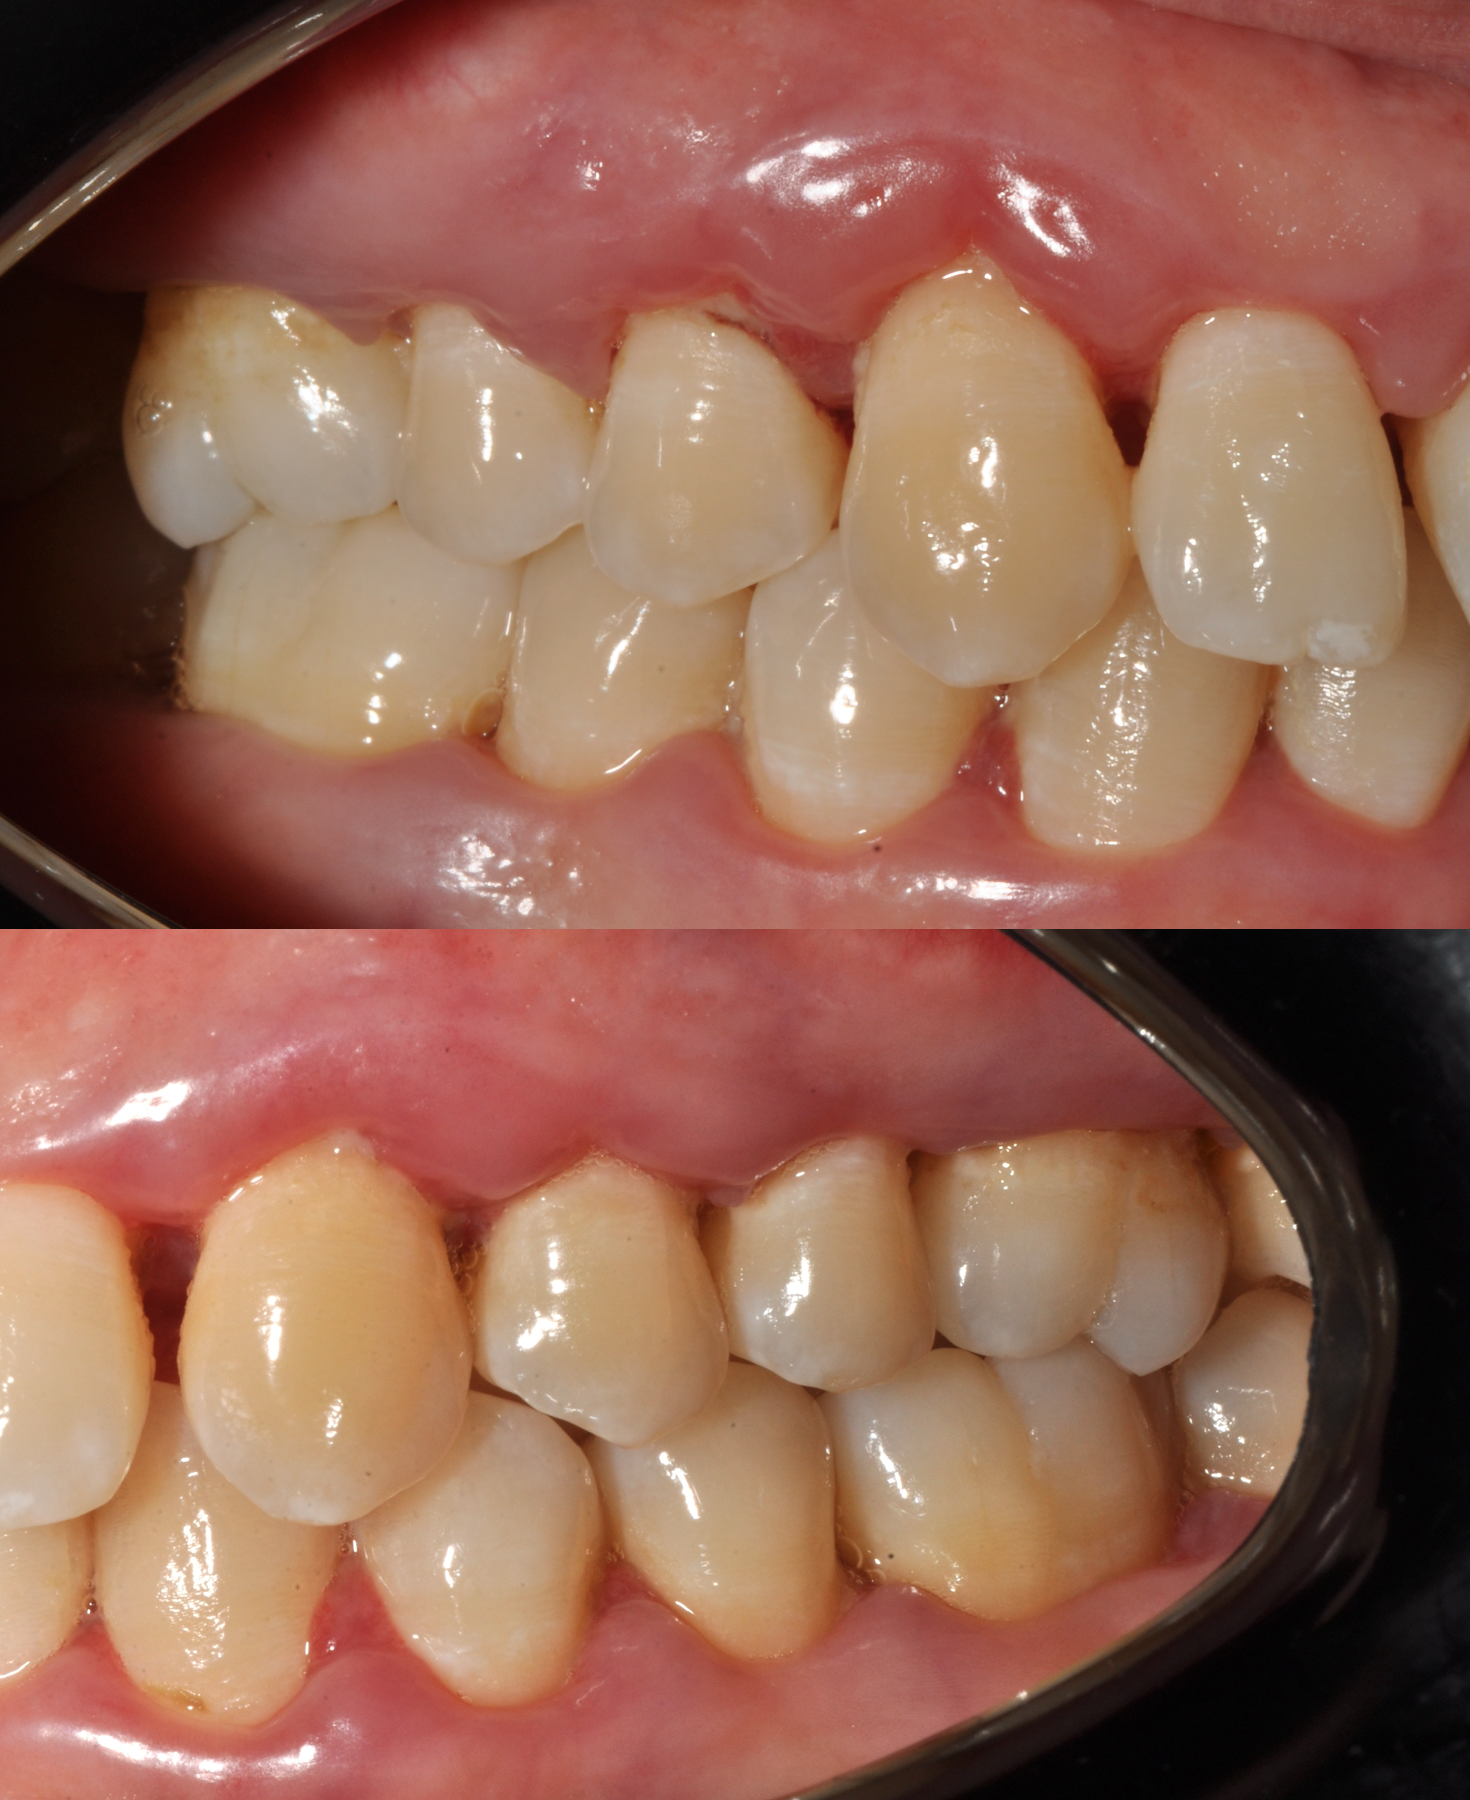

Le immagini cliniche del prima e dopo trattamento e il test di placca al 100% che accompagnano questo articolo mostrano visivamente quanto sia determinante il controllo del biofilm nella guarigione dei tessuti.

L’inquadramento diagnostico: status radiografico e sondaggio parodontale (foto in calce)

Prima e dopo: cosa dimostrano le immagini

Le fotografie cliniche allegate mostrano:

• Gengive infiammate e sanguinanti prima della terapia

• Riduzione dell’edema e dell’eritema dopo la decontaminazione

• Miglioramento della salute gengivale senza incisioni chirurgiche

L’immagine del test di placca al 100% è particolarmente significativa: quando tutto è colorato, significa che il biofilm è ovunque. È da lì che bisogna partire.